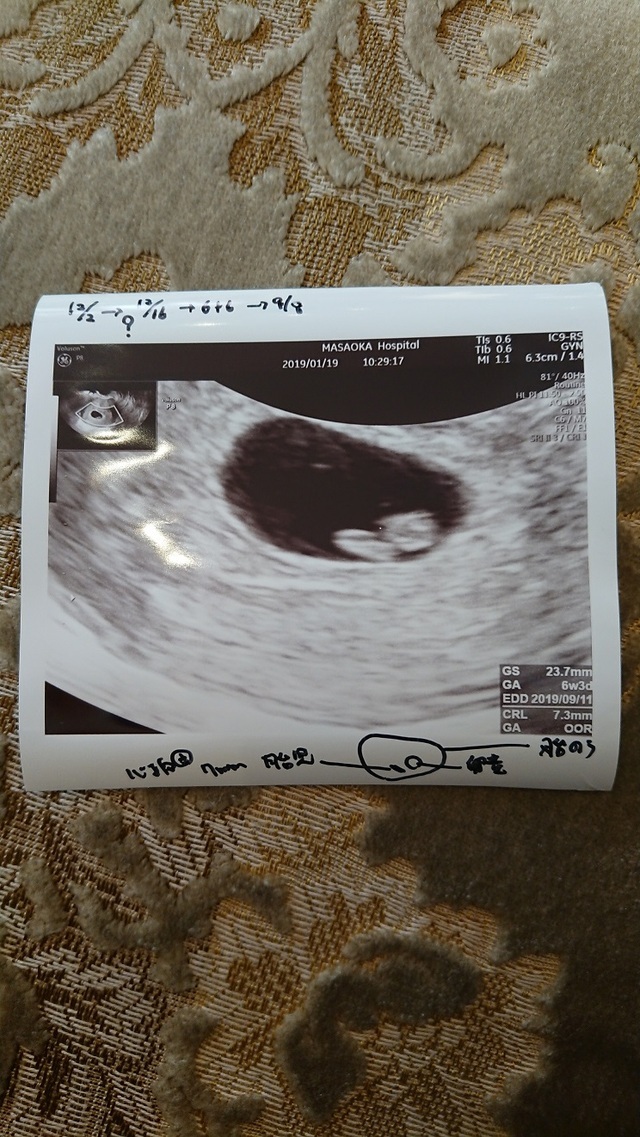

6週2日(6w2d・男の子)|じゅんぺまま さん(27歳)

エコー写真撮影時のエピソード:

2回の流産を経て、3回目の妊娠発覚後初めてのエコー写真。今まで見ることのできなかった心拍の動きにとても感動したことを覚えています。

その時すでに悪阻があり体調的には辛かったのですが、「悪阻がある=お腹の赤ちゃんが元気である」と気持ちの面では勇気付けられていました。

流産を経験しているので妊娠しても周りには伝えず、主人と喜びと不安を分け合いながら過ごしていました。